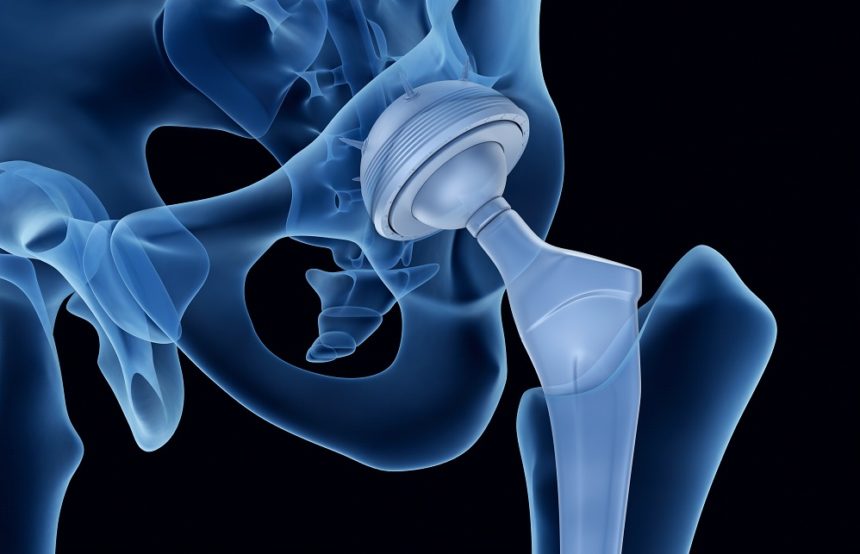

• Χειρουργικής Ισχίου, με έμφαση στην αρθροπλαστική

Συμμετείχε σε ετήσια βάση, σε διεθνή ιατρικά συνέδρια όπως επίσης και σε πτωματικά σεμινάρια για την εκμάθηση νέων χειρουργικών τεχνικών. Εξειδικεύτηκε στη διάγνωση και αντιμετώπιση παθήσεων και κακώσεων με ιδιαίτερη έμφαση στη αρθροσκοπική τεχνική και την αρθροπλαστική. Σημαντικό μέρος της πρακτικής του αποτέλεσε και το ορθοπαιδικό τραύμα όπως τα κατάγματα και οι αθλητικές κακώσεις καθώς εργάστηκε ως επιμελητής ειδικός Χειρουργός σε Τριτοβάθμια Νοσοκομεία και Μείζονα Κέντρα αναφοράς Τραύματος ενεργό μέλος πολυδύναμων ιατρικών ομάδων.